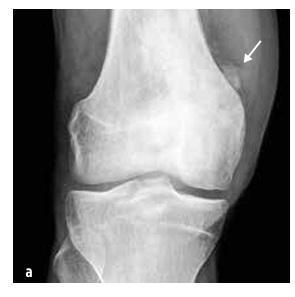

Maligne novotvorine

Kod djece najčešći su osteosarkom (55%, vidi Sliku 5) i Ewingov sarkom (35%, vidi Sliku 6), dok je hondrosarkom izuzetno rijedak. U ovu skupinu također spadaju sarkomi mekih tkiva (rabdomiosarkom i neralabdomiosarkomi), mesenchimski stanični tumori, ekstraskeletni Ewingov sarkom, sinovijalni sarkom, fibrosarkom i embrionalni sarkom.

Slika 5

Osteosarkom distalne femurne trećine